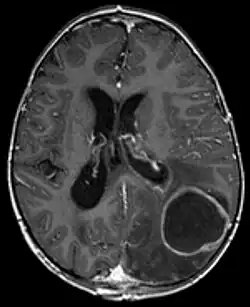

Die körpereigene Abwehr (Immunität) führt zu einer Einschmelzung des hochgradig infizierten Gewebes und zur Abgrenzung gegen das umgebende Gewebe. Dadurch entsteht ein Abszess, der Hirnabszess oder Gehirnabszess[2] (auch zerebraler Abszess[3]). Zugrunde liegen können ein Trauma (traumatischer Abszess), eine Fortleitung auf dem Lymphweg (fortgeleiteter Abszess) oder auf dem Blutweg (metastatischer Abszess).[4] Bei diesem Vorgang kommt es zur Volumenzunahme (Raumforderung), die aufgrund der knöchern begrenzten Schädelhöhle rasch zur Drucksteigerung mit schweren Komplikationen (z. B. Einklemmung) führen kann. Beim Hirnabszess werden vier Stadien[5] mittels Computertomografie unterschieden:

- frühe „Zerebritis“ (Gehirnentzündung): unscharf begrenzte Hypodensität

- späte „Zerebritis“: Hypodensität mit zentraler scharf begrenzter ringförmiger Kontrastmittel-Anreicherung

- frühe Kapselbildung

- späte Kapselbildung: bereits ohne Kontrastmittelgabe als flaue Hyperdensität mit zentraler Hypodensität sichtbar.

Zunächst ist eine bildgebende Untersuchung erforderlich, die zumeist mittels kontrastmittelgestützter Computertomographie oder Magnetresonanztomographie erfolgt. Hier sind in den meisten Fällen der entzündliche Herd, das umgebende Ödem sowie eine Anreicherung des Kontrastmittels zu erkennen.